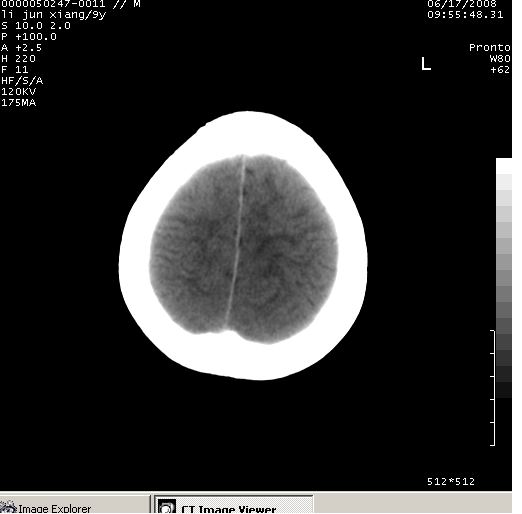

颅脑ct轴位平扫(层厚、层距均为10mm),图像如下:

调骨窗:颅骨未见明确异常。

只是双侧脑室不对称,其它未见异常啊